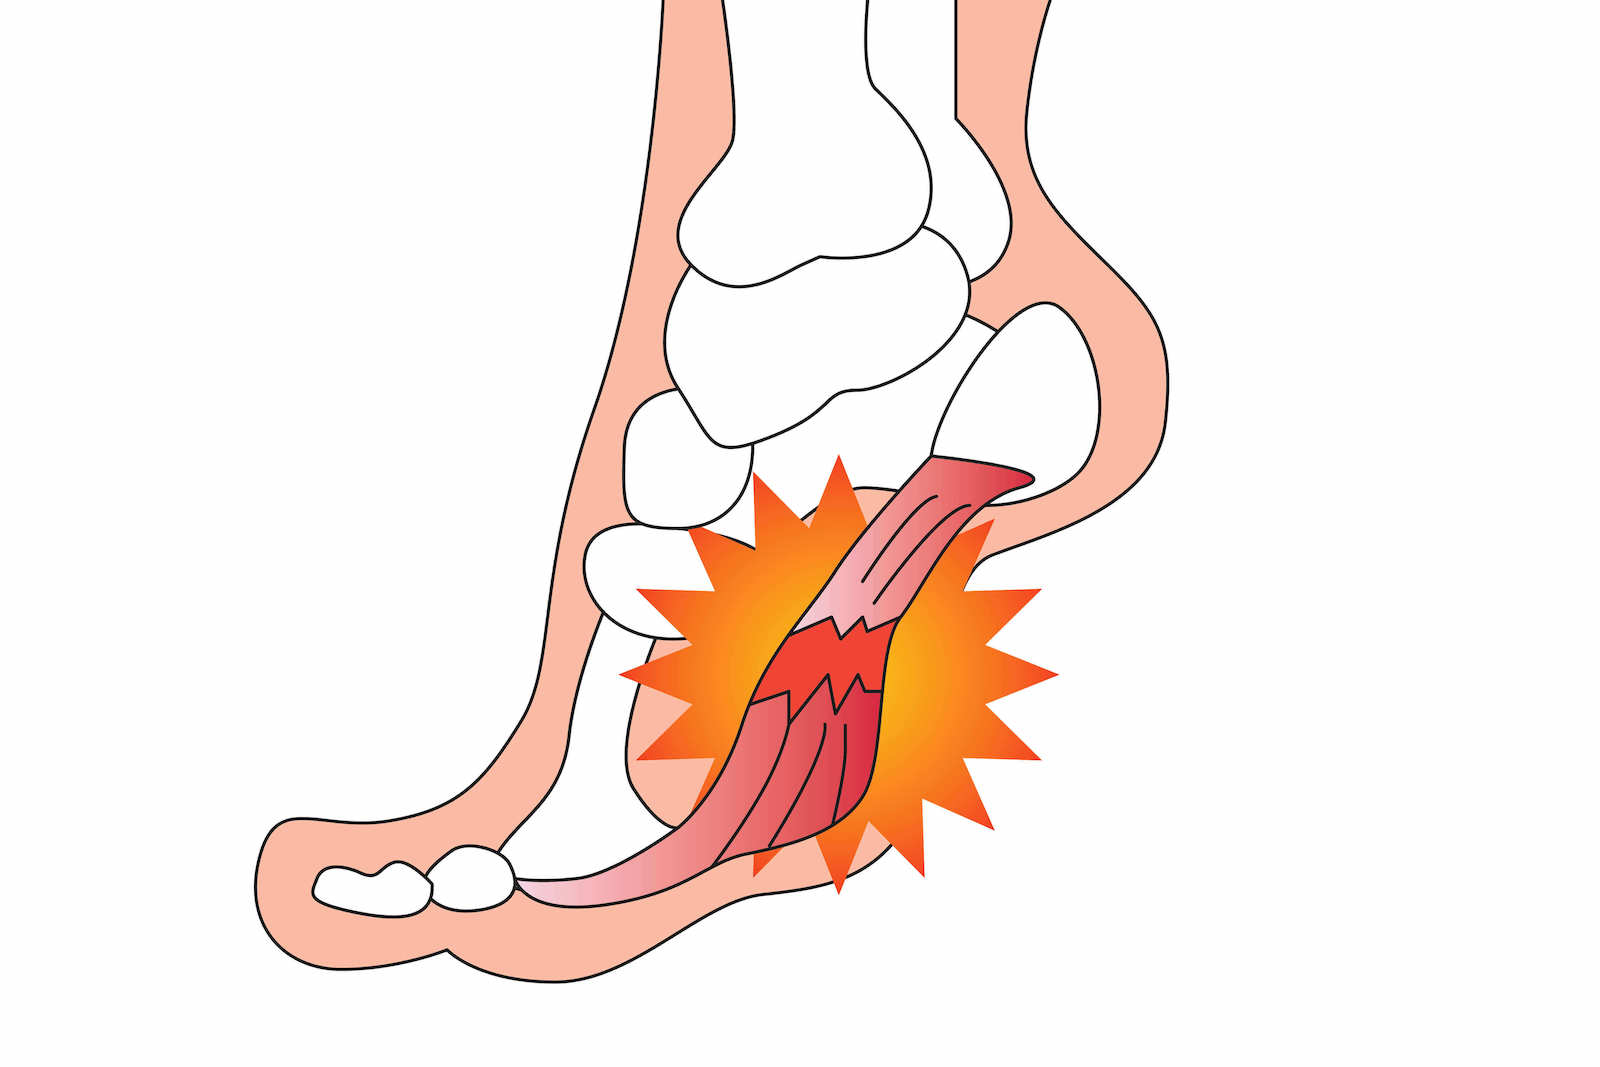

足底筋膜炎は、かかとや足の痛みの一般的な原因です。幸いなことに、自宅でできるストレッチや足のマッサージは痛みを和らげ、症状の慢性化を防ぐのに役立つ可能性があります。

腓腹筋とヒラメ筋として知られるふくらはぎの筋肉は、アキレス腱に接続しています。これらのふくらはぎの筋肉は、特によく立ったり、走ったり、ハイヒールを履いたりする場合に硬くなることがよくあります。これは足底筋膜炎の一因となる可能性があり、ふくらはぎのマッサージは足の痛みを和らげるのに役立ちます。

「マッサージセラピストは深部組織マッサージを行うことができます」とパーソンズ氏は言います。 「ふくらはぎから始めて、ふくらはぎの裏側と外側の非常に深い筋肉を鍛えます。次に、足の裏の腱と筋肉にアプローチします。マッサージトリートメントには、揉みほぐし、筋膜リリース、筋エネルギーテクニック、位置リリース、トリガーポイントセラピー、ピンとストレッチが含まれます。これらすべてを一度に行うのではなく、1 つ以上のテクニックで痛みが軽減されるまで続けます。」